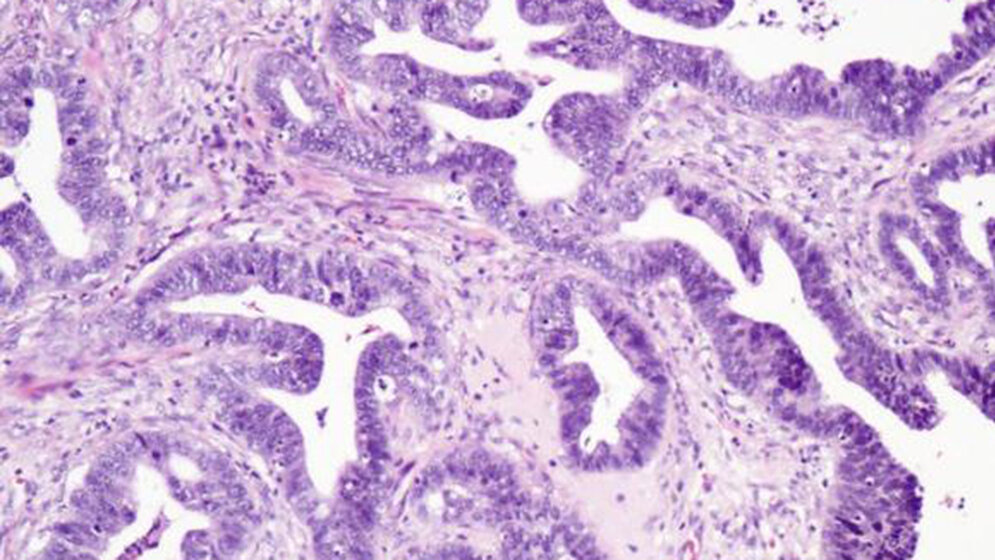

Carcinoma cervicis uteri und seine Vorstufen